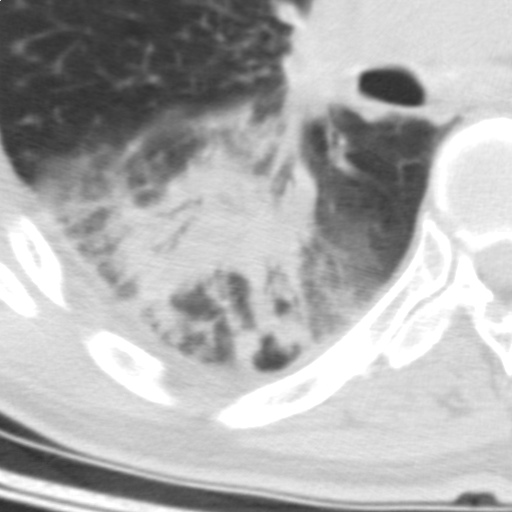

以下是引用随光逐影在2009-5-1 13:53:00的发言:[br]考虑为:1)两肺血行播散型肺结核;2)右肺下叶炎症感染。3)右侧胸膜增厚。